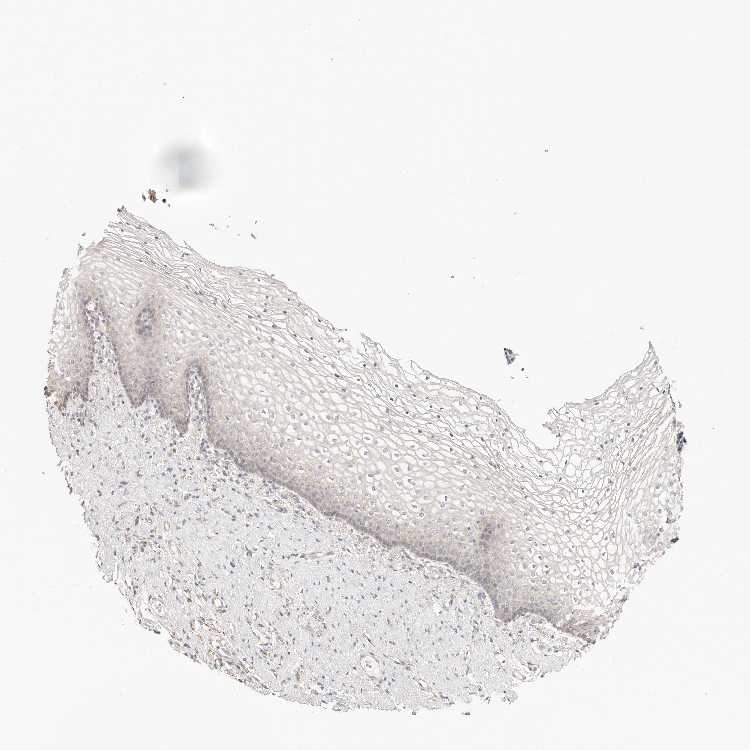

TISSUE PRIMARY DATA VAGINA Show tissue menu

VAGINA - Antibody stainingi

Antibody staining in the annotated cell types in the current human tissue is reported as not detected, low, medium, or high, based on conventional immunohistochemistry profiling in selected tissues. This score is based on the combination of the staining intensity and fraction of stained cells.

Each image is clickable and will lead to virtual microscopy that enables deeper exploration of all samples and also displays staining intensity scores, fraction scores and subcellular localization as well as patient and tissue information for each sample.

Antibody HPA030212Antibody HPA030213Antibody HPA030214Antibody HPA030215Antibody CAB013496

Squamous epithelial cells MediumMediumLowMediumNot detected